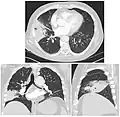

El diagnóstico se realiza, fundamentalmente y dentro de un contexto clínico, por la radiografía de tórax.

Radiografía de tórax de una neumonía lobar afectando al lóbulo medio del pulmón derecho derecho. -

TAC del mismo caso.